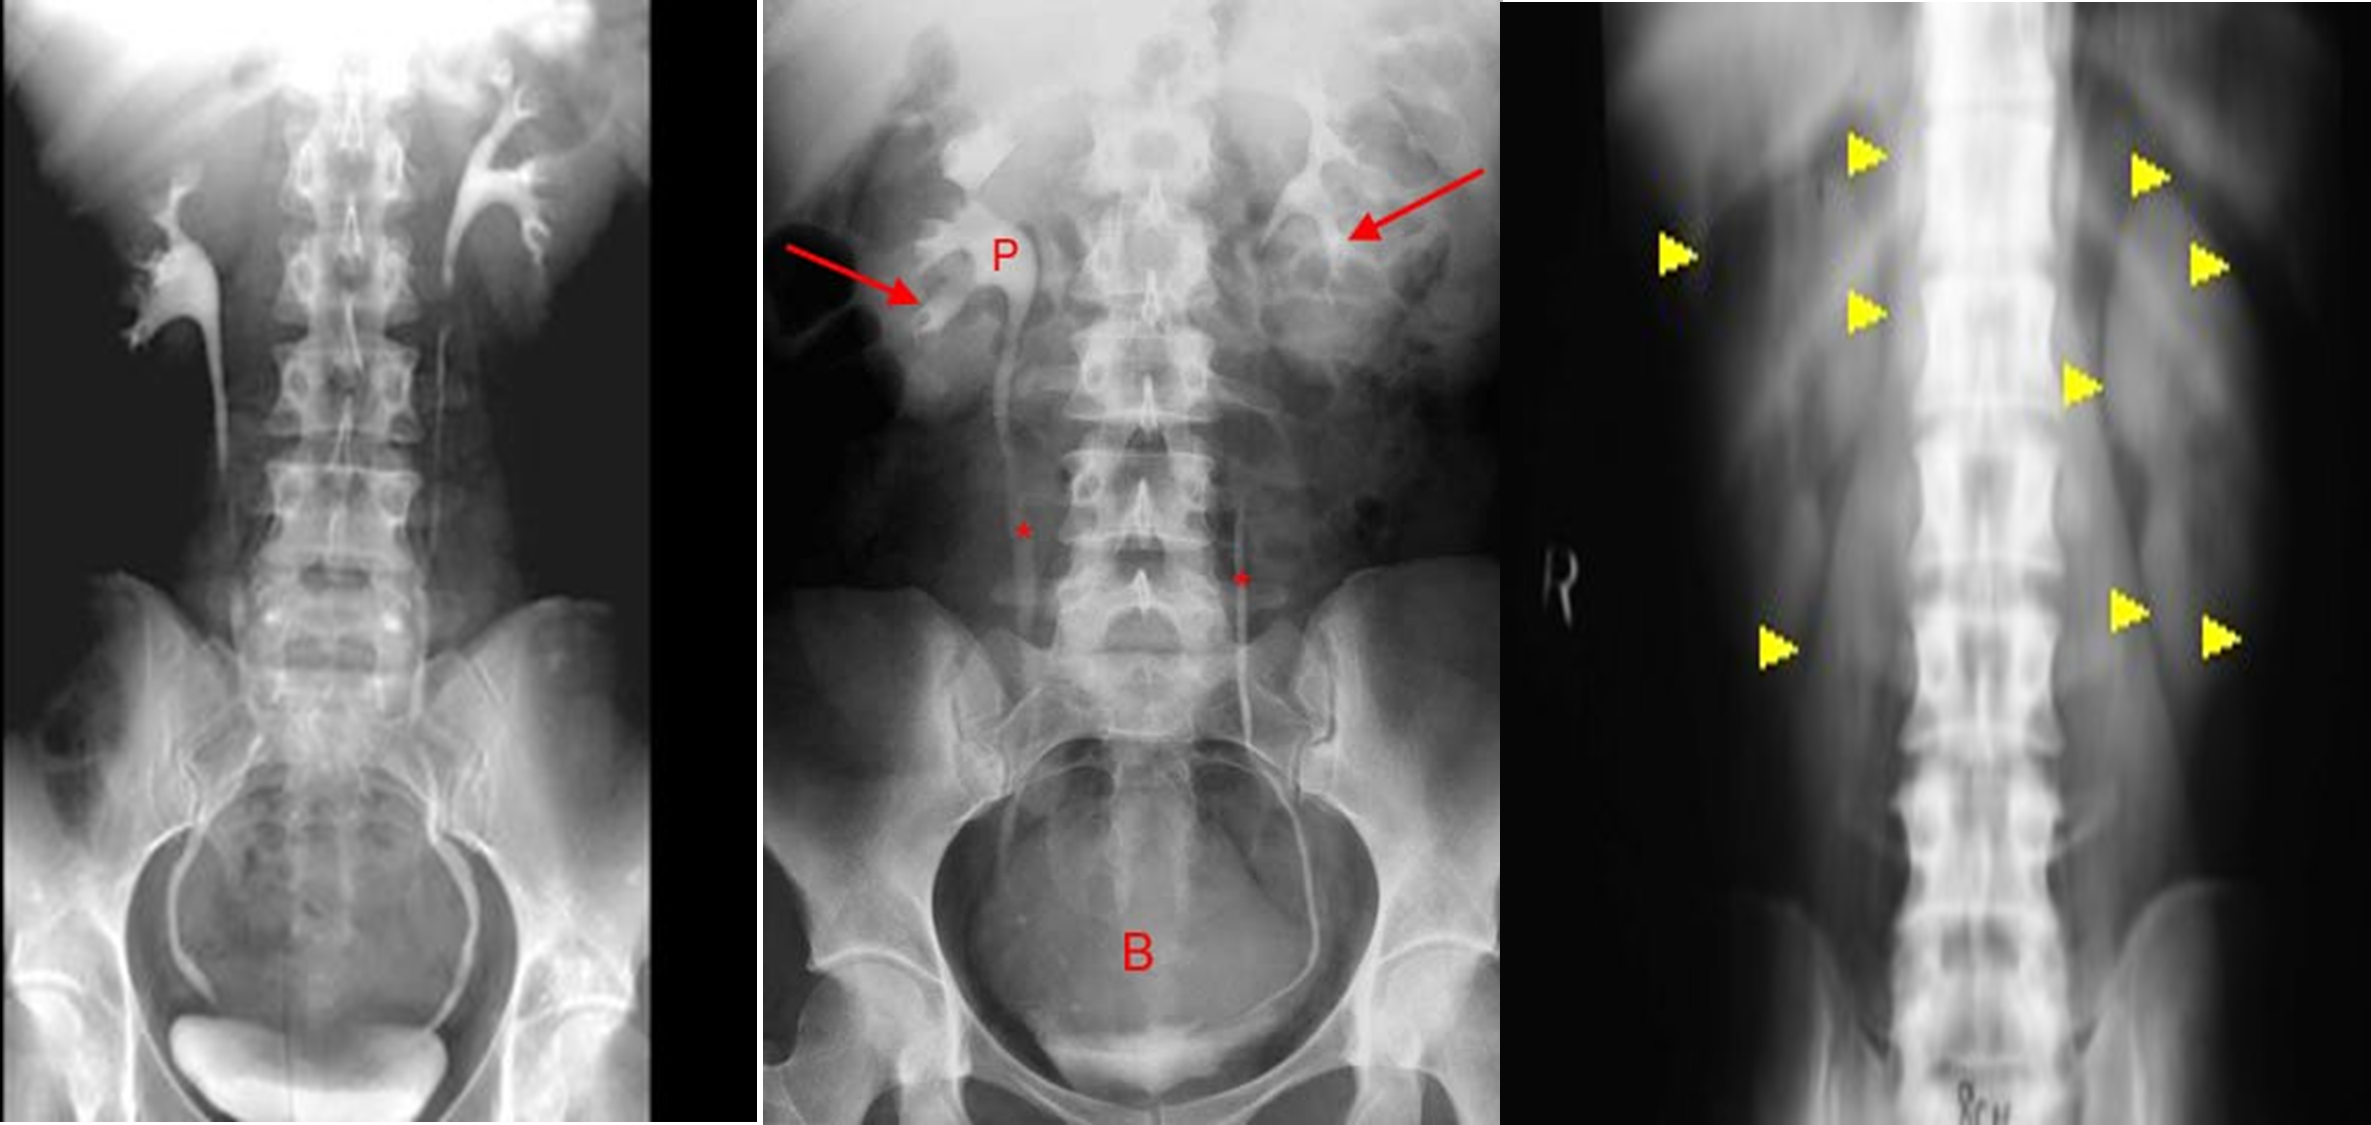

Intravenous urography

is an x-ray examination of the urinary tract consisting of kidneys, ureters and bladder following an injection of contrast into a vein in the arm.

Scout film ( abd. ) , Scout film is also called KUB

- Supine ,oblique , prone upright and post void film are taken

Rarely indicated given the broad availability of CT - Immediate film of the renal areas: AP film of the renal area. Aim to show the nephrogram opacified by contrast in the renal tubules.